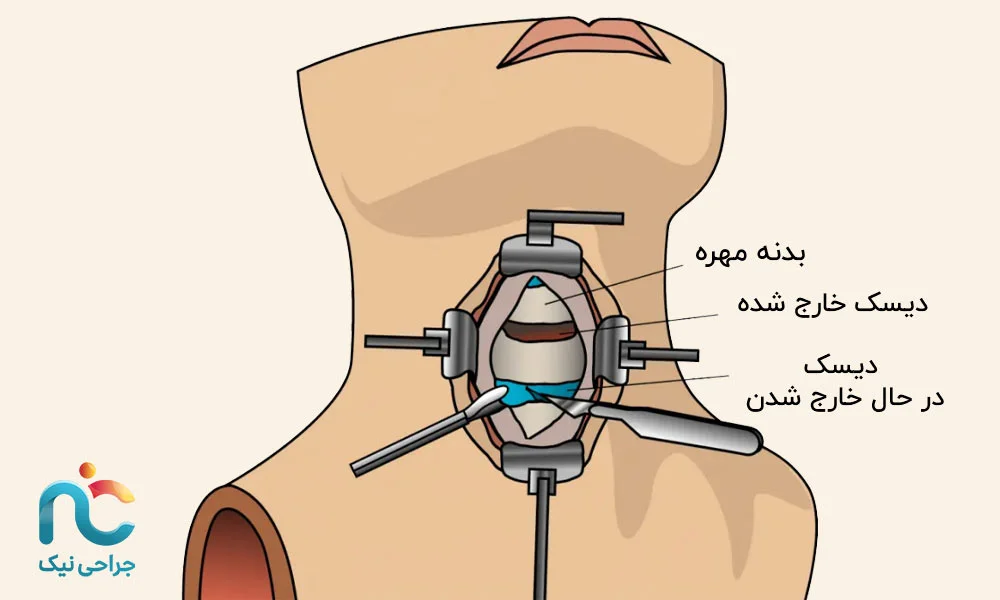

۱. روش قدامی (Anterior Approach)

در این روش، جراح از جلوی گردن وارد میشود. این مسیر اجازه میدهد بدون دست زدن به عضلات و استخوانهای پشت گردن، مستقیماً به دیسک برسد. معمولاً برای بیرونزدگیهای مرکزی یا مواردی که فشار روی نخاع وجود دارد از این مسیر استفاده میشود. برش بسیار کوچک است و بعد از عمل، جای زخم تقریبا نامشخص میماند.

در جراحی اندوسکوپیک دیسک گردن، برخلاف تصور بسیاری از بیماران، هدف این نیست که کل دیسک از بدن خارج شود. در واقع، پزشک تنها بخش فتقکرده یا همان قسمت بیرونزدهی دیسک را که روی عصب فشار میآورد، با ابزارهای ظریف و از طریق یک دوربین مخصوص خارج میکند. این بخش همان جایی است که باعث درد، گزگز یا بیحسی میشود. قسمتهای سالم دیسک که هنوز انعطاف و عملکرد خود را دارند، تا جای ممکن حفظ میشوند تا گردن بتواند حرکت طبیعی خود را بعد از عمل حفظ کند. به همین دلیل است که پس از جراحی، بیمار هنوز بین مهرهها دیسک دارد، فقط دیگر آن فشار آزاردهنده روی عصب وجود ندارد.